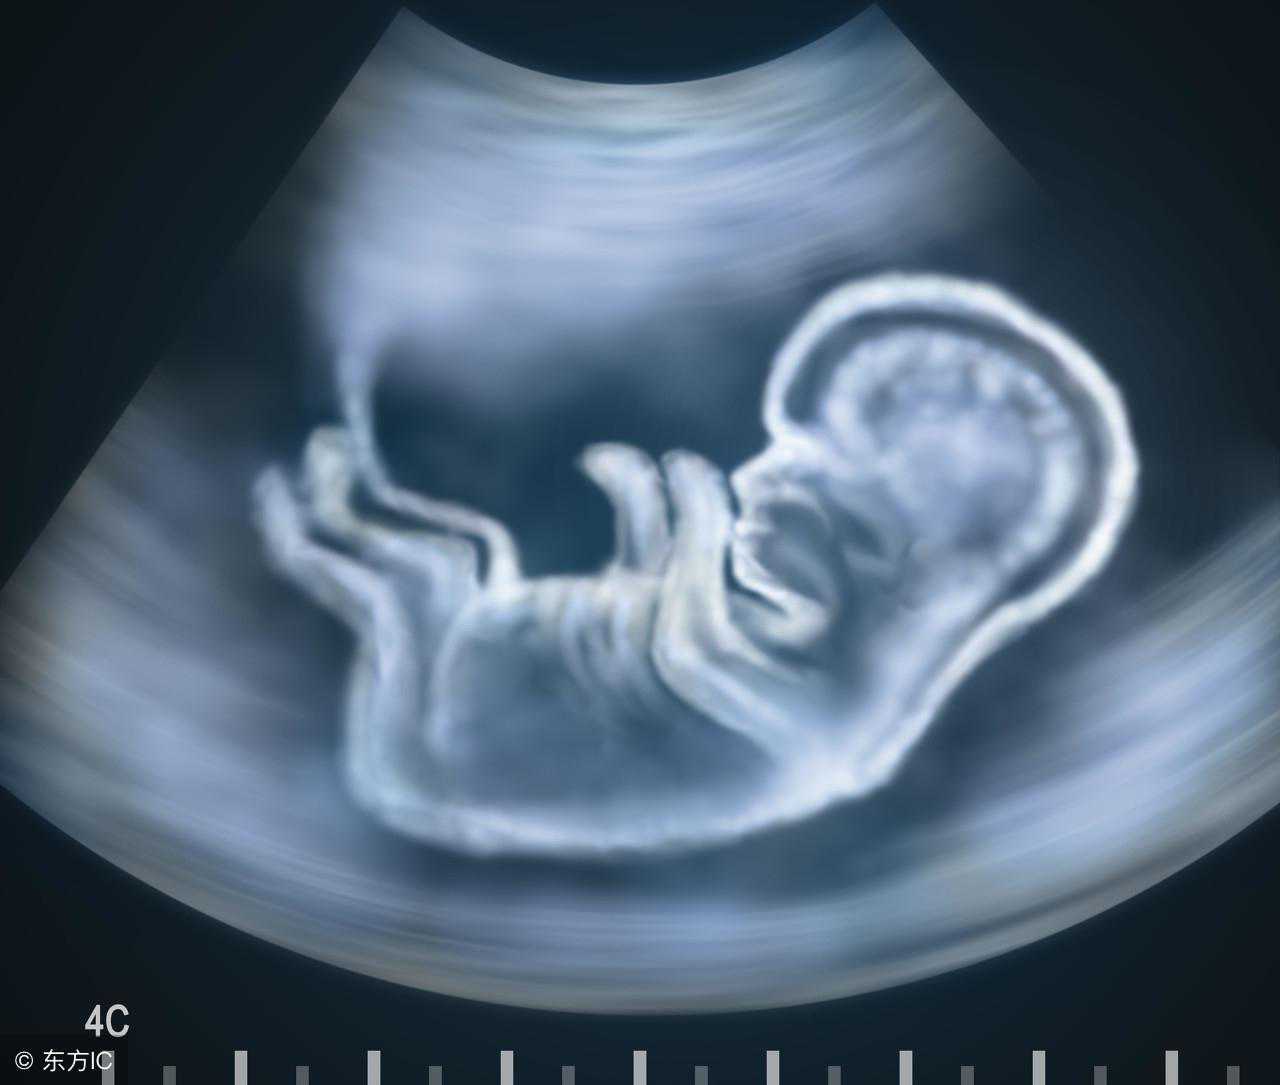

妊娠是一个复杂的过程,卵子受精后,进入宫腔,胚胎及附属物迅速生长发育直至成熟的过程中,每个孕周都会有不同的变化。每次我们去医院B超单上各组数据就是看不懂,问医生也不可能什么都问到,这篇文章帮你看懂自己的B超单!

8周:胎儿长到1.66厘米,胎形已定,可分出胎头、体及四肢,胎头大于躯干。B超可见胎囊约占官腔1/2,胎儿形态及胎动清楚可见,并可看见卵黄囊。

9周:胎儿长到2.15厘米,胎儿头大于胎体,各部表现更清晰,头颅开始钙化、胎盘开始发育。B超可见胎囊几乎占满宫腔,胎儿轮廓更清晰,胎盘开始出现。

10周:胎儿长到2.83厘米,胎儿各器官均已形成,胎盘雏形形成。B超可见胎囊开始消失,月芽形胎盘可见,胎儿活跃在羊水中。

11周:胎儿长到3.62厘米,胎儿各器官进一步发育,胎盘发育。B超可见胎囊完全消失,胎盘清晰可见。

12周:胎儿长到4.58厘米,外生殖器初步发育,如有畸形可以表现,头颅钙化更趋完善。颅骨光环清楚,可测双顶径,明显的畸形可以诊断,此后各脏器趋向完善。